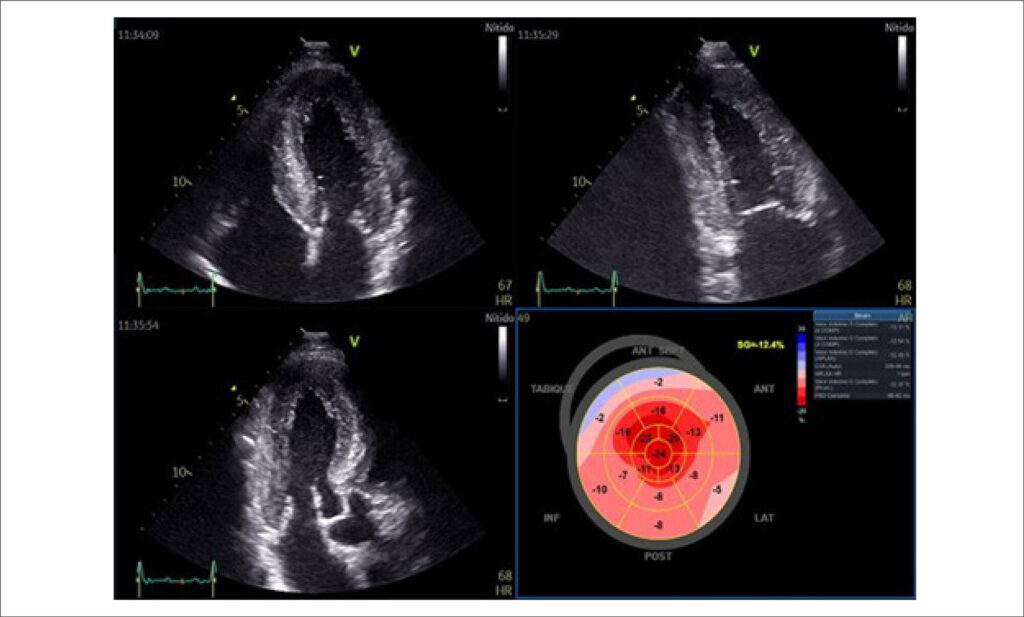

There are two distinct forms of ATTR: hereditary, caused by pathogenic mutations that destabilize the protein, and acquired, also known as wild-type (wtATTR), which results from the accumulation of wtATTR protein. Regarding clinical manifestations of ATTR, in the case of the hereditary type, they depend on the genetic variant involved and can lead to cardiac and extracardiac involvement, including sensory-motor peripheral neuropathies, autonomic neuropathies, gastrointestinal manifestations, among others. In the case of wtATTR, cardiac involvement is the predominant manifestation, characterized by heart failure, conduction disorders, and arrhythmias. The gold standard for diagnosis of cardiac amyloidosis is the demonstration of apple-green birefringence in polarized light microscopy of Congo red-stained tissue. However, confirmatory biopsy is no longer necessary for a diagnosis when the following criteria are met: heart failure with an echocardiogram or cardiac magnetic resonance imaging consistent with amyloidosis, a grade 2 or 3 uptake on radionuclide scintigraphy with 99m-Technetium-labeled 3,3-diphosphono-1,2-propanodicarboxylic acid or pyrophosphate (PYP), and absence of a detectable monoclonal gammopathy. There are currently new disease-modifying therapeutic options available for both hereditary and acquired ATTR. Among the available drugs are selective TTR stabilizers, such as tafamidis, and genetic silencers, such as inotersen or patisiran, which provide the most significant benefit in the early stages of the disease.